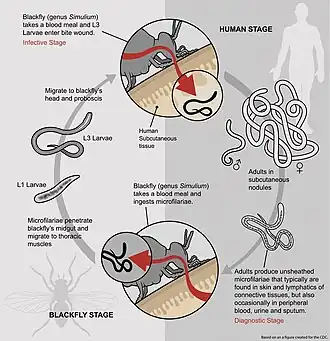

Blackfly stages

- The microfilariae of O. volvulus are found in the dermis layer of skin in the host.

- When a female Simulium blackfly takes a blood meal from an infected host, the microfilariae are also ingested.

- From here, the microfilariae penetrate the gut and migrate to the thoracic flight muscles, where they enter the first juvenile phase, J1.

- After maturing into J2, the second juvenile phase, they migrate to the proboscis, where they are found in the saliva.

- J2 stage juveniles then mature into infectious stage three juveniles, J3, in the saliva. The lifecycle in the blackfly takes between one and three weeks.[11]

Human stages

- When the female blackfly takes a blood meal, J3 juveniles pass into the human bloodstream.

- From here, the juveniles migrate to the subcutaneous tissue, where they form nodules and mature into adult worms over a period of 6–12 months.

- After maturation, the smaller adult males migrate from nodules to subcutaneous tissue, where they mate with the larger adult females.

- The eggs mature internally to form stage-one microfilariae, which are released from the female's body one at a time and remain in the subcutaneous tissue.

- The microfilariae are taken up by a female blackfly when it takes a blood meal, thus completing the lifecycle of O. volvulus.[5]